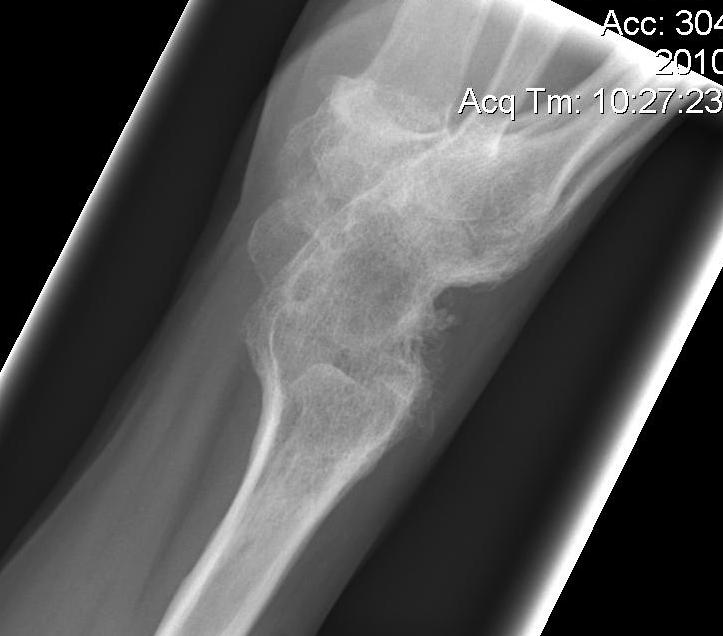

Xray

End stage disease

- arthrodesis

- arthroplasty

Wrist arthrodesis

Total wrist arthrodesis

Indications

Diffuse advance radiocarpal and mid carpal OA

Poor bone stock

Stiff wrist

Loss of wrist extensors

High demand